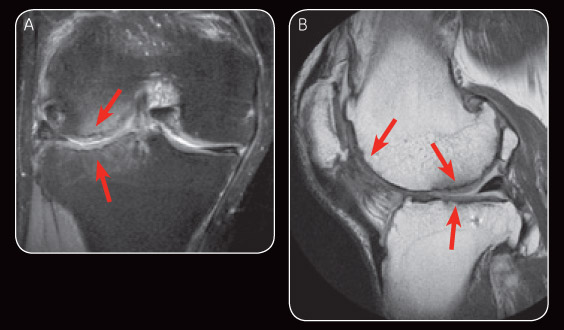

Fig. 3 Appearance on MR image at six-month follow-up demonstrates satisfactory repair cartilage and minimal subchondral oedema (A). Sagital PD at six-month follow-up also demonstrates satisfactory repair cartilage (B).

Interval MR exams by 1.5T ONI MSK Extremity MR has shown satisfactory healing of the chondral defects including the subchondral bone. The MR images also clearly showed evidence of cartilage regeneration. This newfound innovative procedure is not limited to small isolated lesions but can be used to treat large, multi-compartment lesions, including “kissing lesions.”